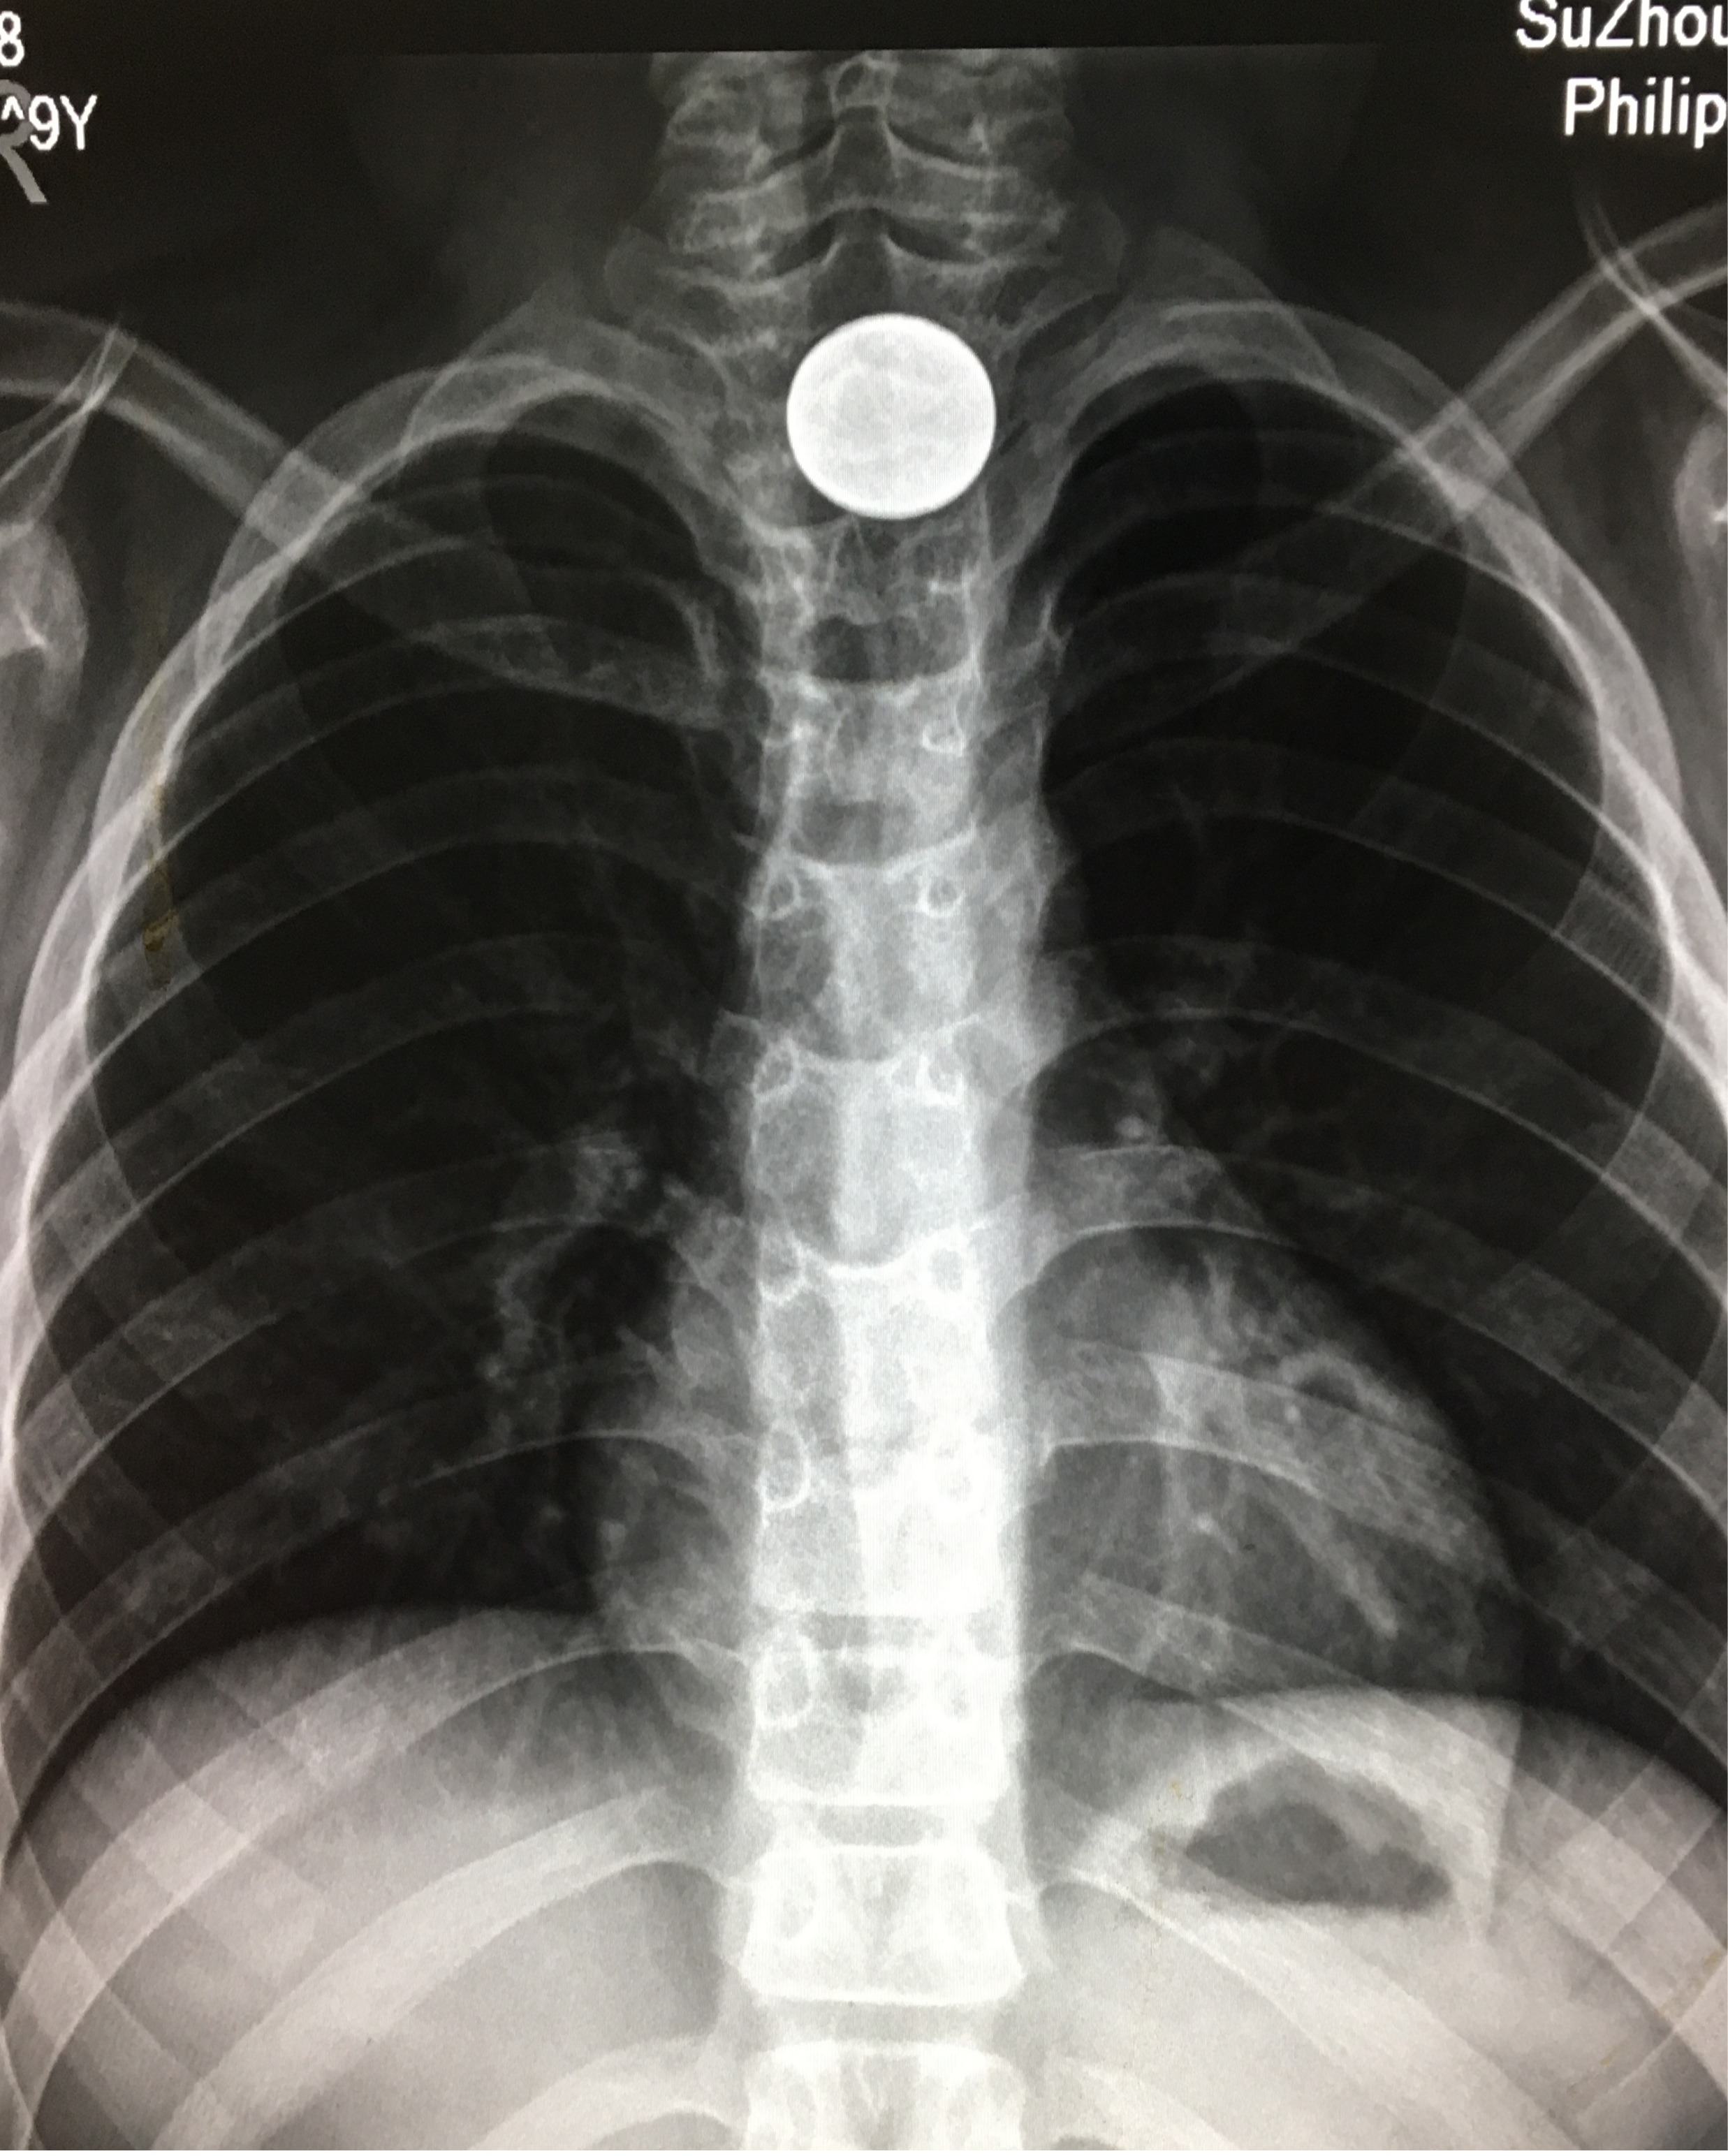

因误吞一元硬币苏州九岁女孩被卡得面红耳赤

图片尺寸2474x3087